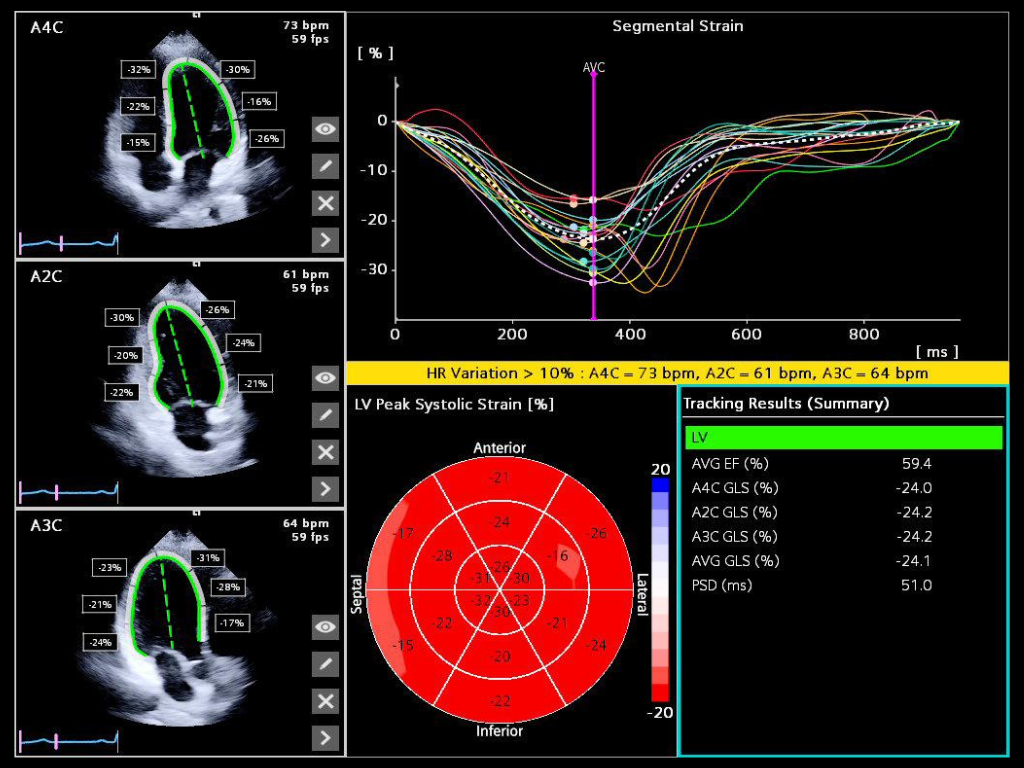

- 4D HeartAI utilizes proprietary AI to process complex cardiac data, 4D analysis, and imaging for TTE and TEE for timely and accurate decision making.

- AI Assist alleviates time consuming echo calculations and standardize exams across users.